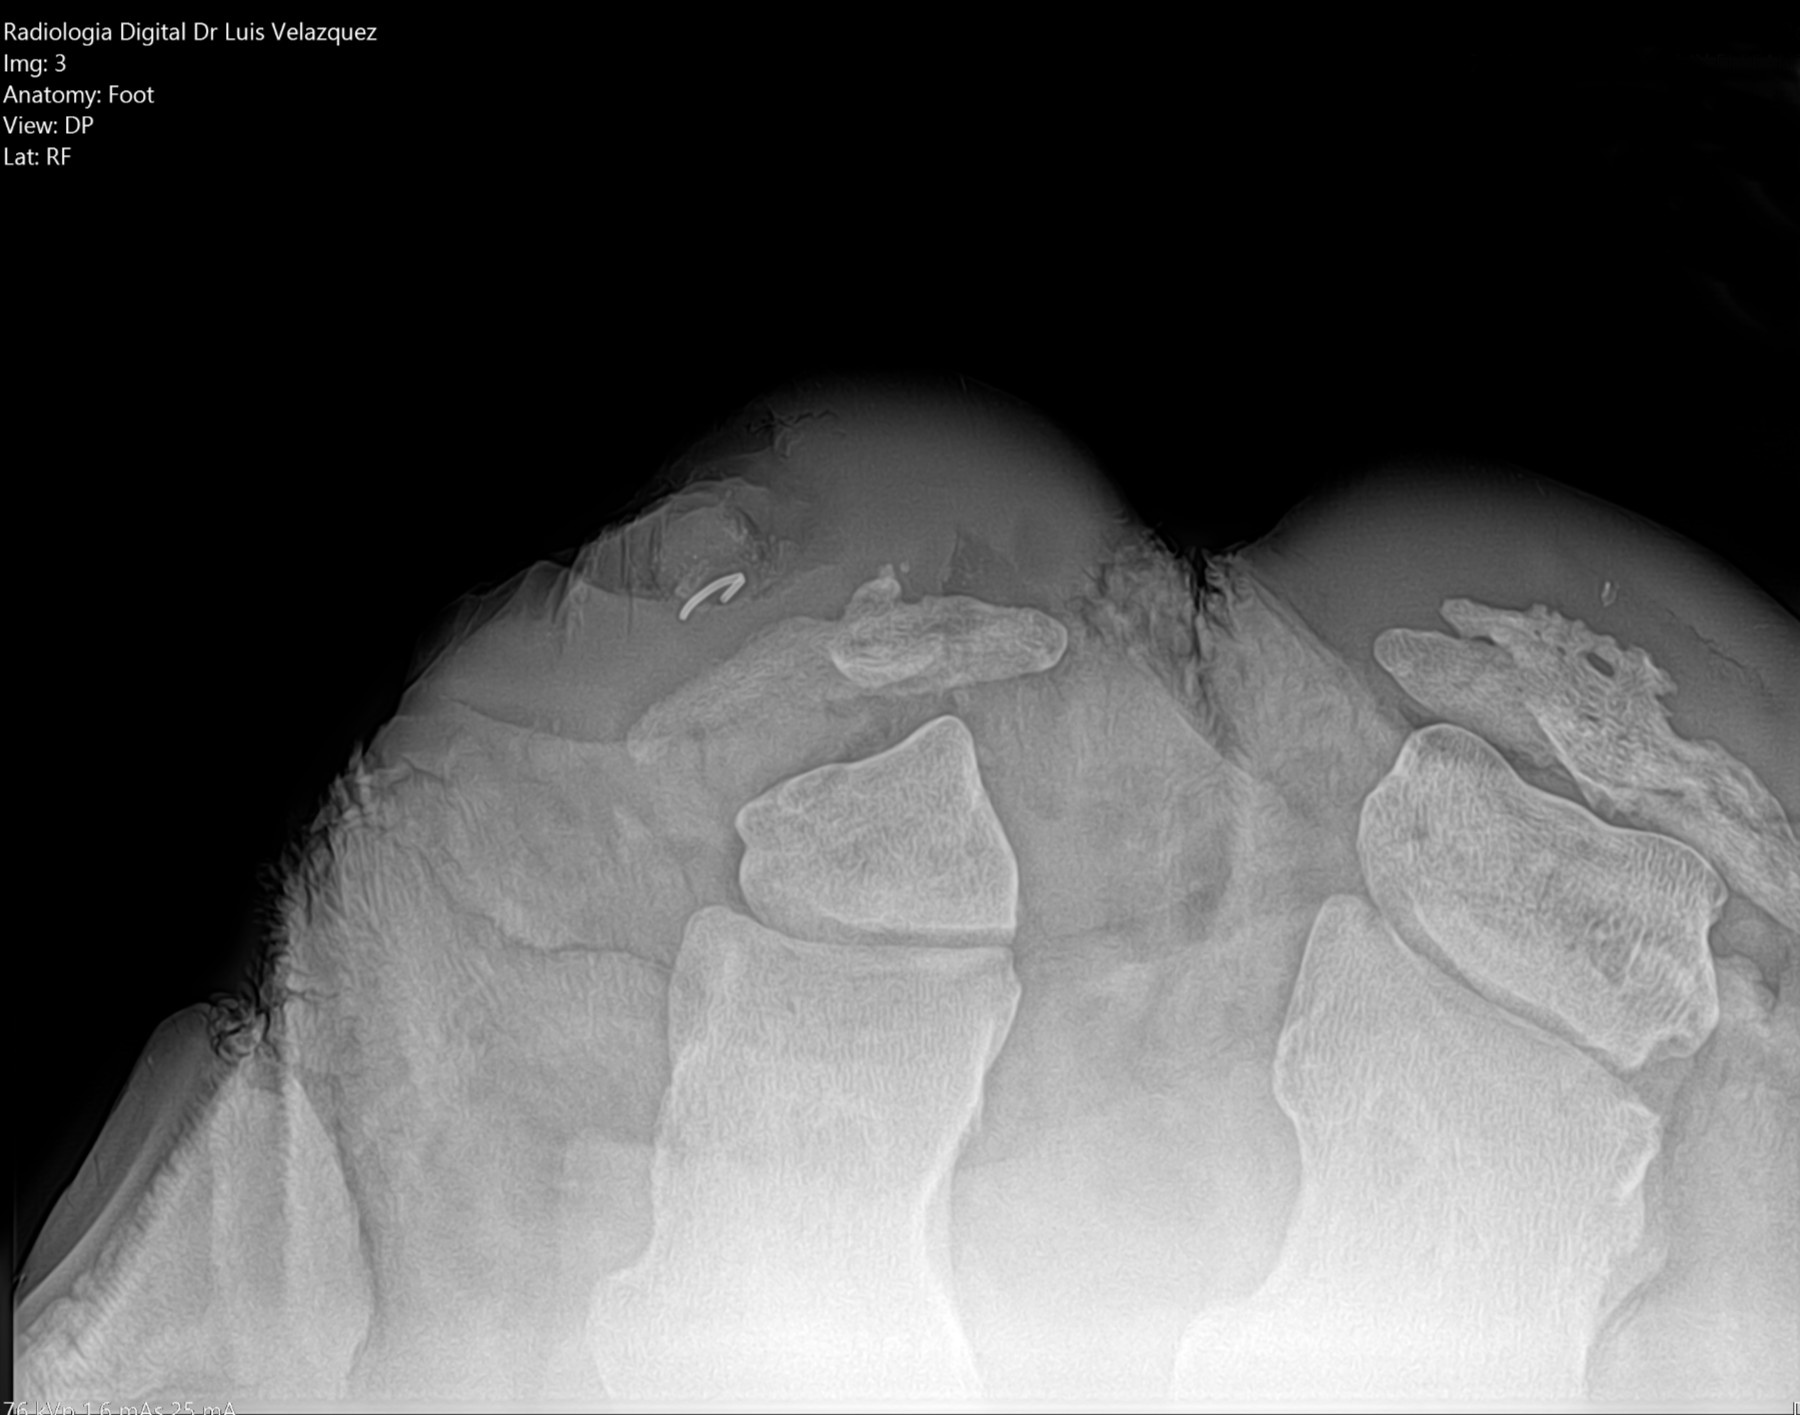

Cambios Térmicos en las Extremidades de Caballos,

Asociados a Golpes y su Evaluación por Termografía.

Los caballos de salto, en competencia, pueden derribar obstáculos y lastimarse. Si se golpean, no siempre claudican. Considerando al calor como un signo de inflamación, se evaluaron los cambios térmicos de 6 áreas de las extremidades torácicas y pelvianas de 23 caballos de salto en nivel de competencia de 1.05 a 1.60 m de altura, por medio de termografía durante 4 días de competencia (N=2208 áreas).